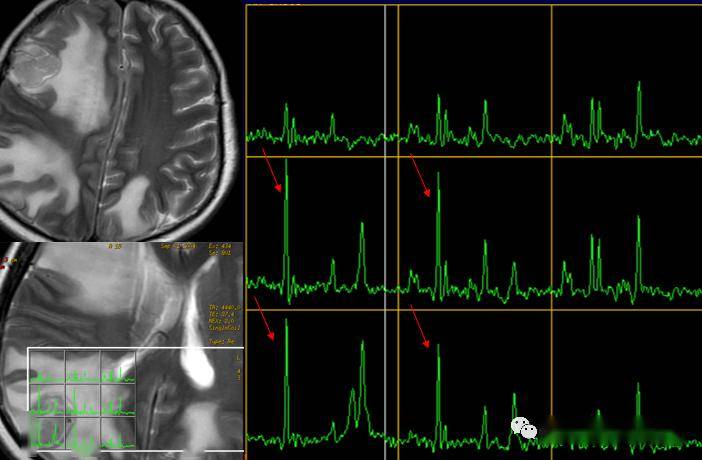

征文作品多参数磁共振波谱成像的应用

图片尺寸960x600